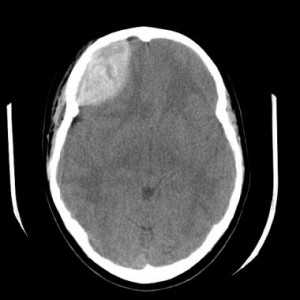

Эпидуральная гематома (экстрадуральная гематома) имеет травматическое происхождение. Это скопление крови внутренний костной пластинкой и твердой мозговой оболочкой. Обычно гематома расположена под областью перелома костей черепа. Причиной кровоизлияния является разрыв оболоченной артерии. Встречаются эпидуральные гематомы вдвое реже субдуральных. По форме гематома двояковыпуклая. Чаще всего диагностируется в неотложных условиях методом КТ. МРТ обычно применяется при спинальных эпидуральных гематомах.

КТ. Эпидуральная гематома.